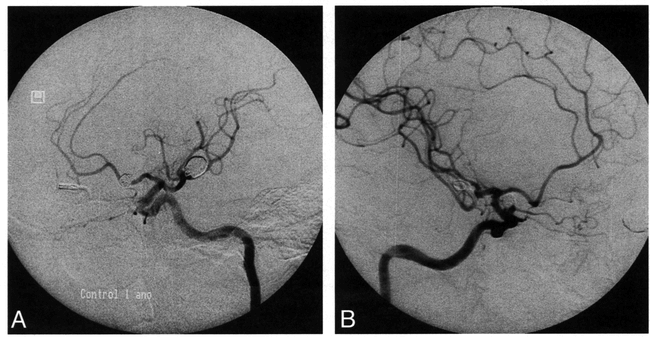

In June 1995, the control angiogram showed that the left MCA aneurysm remained fully occluded. Some coil compaction into the dome of the right carotid ophthalmic aneurysm occurred, resulting in recanalization (Fig 2). We tried to embolize this remnant, but this was not possible because coils protruded into the lumen of the parent artery. A follow-up angiogram was scheduled to occur 12 months after this procedure, but the patient refused further angiographic investigation. Clinical examination at that time was within normal limits.

Left ICA angiogram done 1year after GDC treatment of left MCA. Aneurysm remains completely occluded (A). Right ICA angiogram done 1 year after GDC treatment of right carotid ophthalmic aneurysm (B). There is some coil compaction and a small-neck remnant